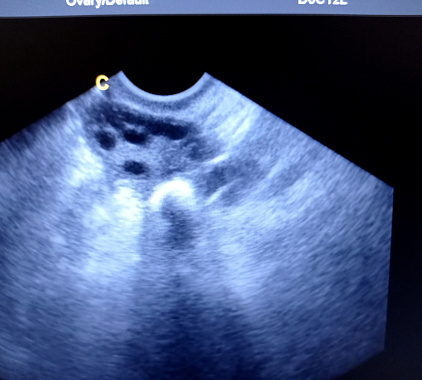

Следующий ориентир — эхогенность структуры. В норме на экране видно овальный контур с ровной, средней по яркости капсулой. В толще коры мерцают крошечные пузырьки-фолликулы диаметром 5–8 мм. Около 8-12-го дня менструального цикла один из них вырывается вперед и увеличивается до 18-24 мм — это будущая овуляция. Если ультразвук проводится после выхода яйцеклетки, вместо него уже просматривается «звездочка» желтого тела 15–25 мм с кольцом мелких сосудов. Лютеиновая фаза сопровождается легким отеком всей ткани, поэтому длина и толщина временами увеличиваются на 1–2 мм — вариант нормы, а не патология.

- Синдром поликистозных яичников (СПКЯ) врач описывает характерной фразой: «ожерелье фолликулов». По периферии ровным кольцом выстроилось не меньше двенадцати пузырьков до 9 мм, капсула при этом утолщена, строма уплотнена и ярче обычного. Если добавить ановуляторные циклы и избыток андрогенов, диагноз практически очевиден.

Фотогалерея